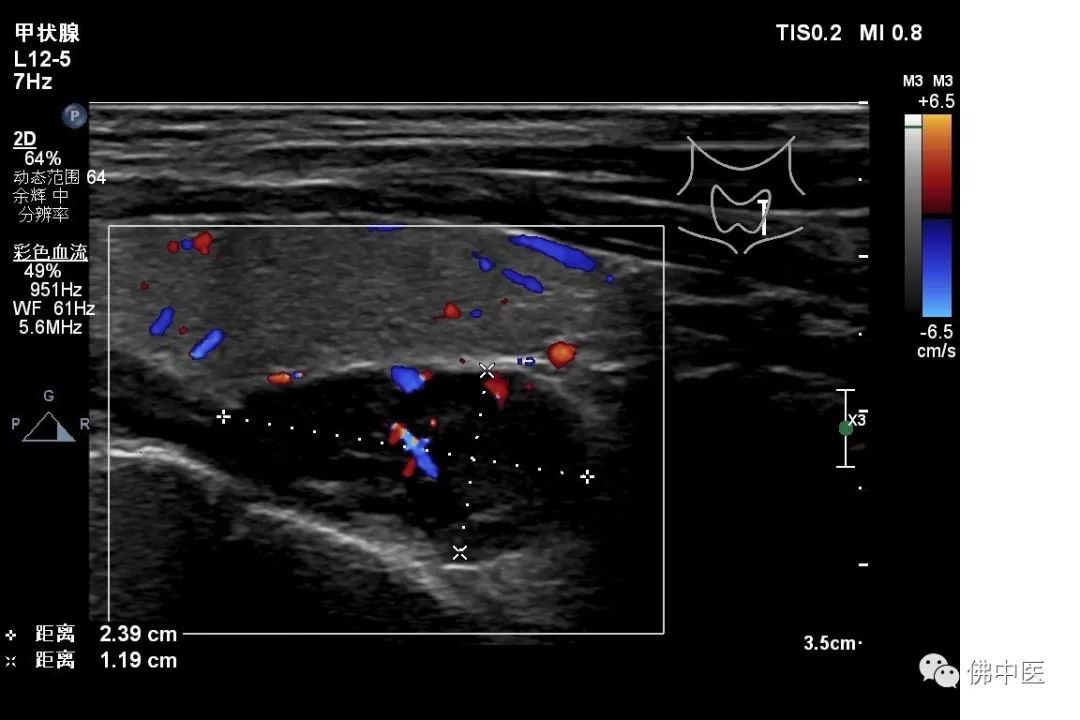

两名患者入院后住院生化检查提示碱性磷酸酶明显升高,血钙升高,但血磷下降,呈钙磷倒置现象,但肿瘤指标均未见明显异常;骨密度检查均提示“骨质疏松”;胸与双肺、全腹平扫+增强CT检查未见明显异常。针对此种具有恶性肿瘤征象,但无明确恶性肿瘤证据的患者,骨病专科主任劳永锵教授建议完善甲状腺彩超检查及甲状旁腺激素测定,结果两例患者甲状旁腺激素均明显升高,甲状腺彩超检查均可发现实性结节。

病例一(甲状腺彩超)